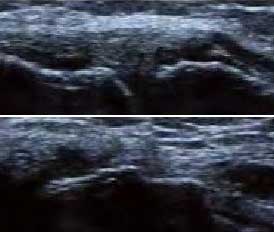

4、具备软组织超高分辨率 区分关节受损层级

肌骨超声通过平面成像能力发现RA关节软骨微小病变,早期就能准确反映出软骨下骨质线回声增高程度,关节软骨表面是否毛糙模糊凹凸不平、形态是否规则、有无明显隆起或缺损形成,判断早期RA软组织改变及RA骨质受损状况。

Ⅰ级

骨表面欠平整骨关节面边缘不整齐、模糊,形成不规则间隙

Ⅱ级

骨质中断或缺失骨表面出现弧形条状低回声,软骨表面不规则变薄、缺损形成

Ⅲ级

骨表面凹凸不平骨表面缺损融合成广泛的骨质破坏、侵蚀